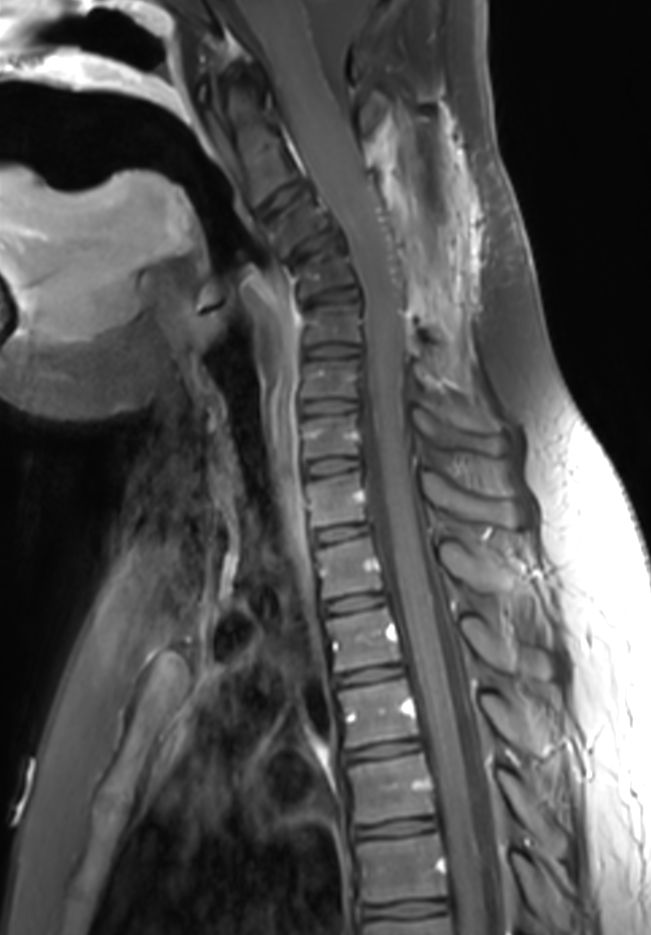

Sagittal T1w TSE (C-Spine)